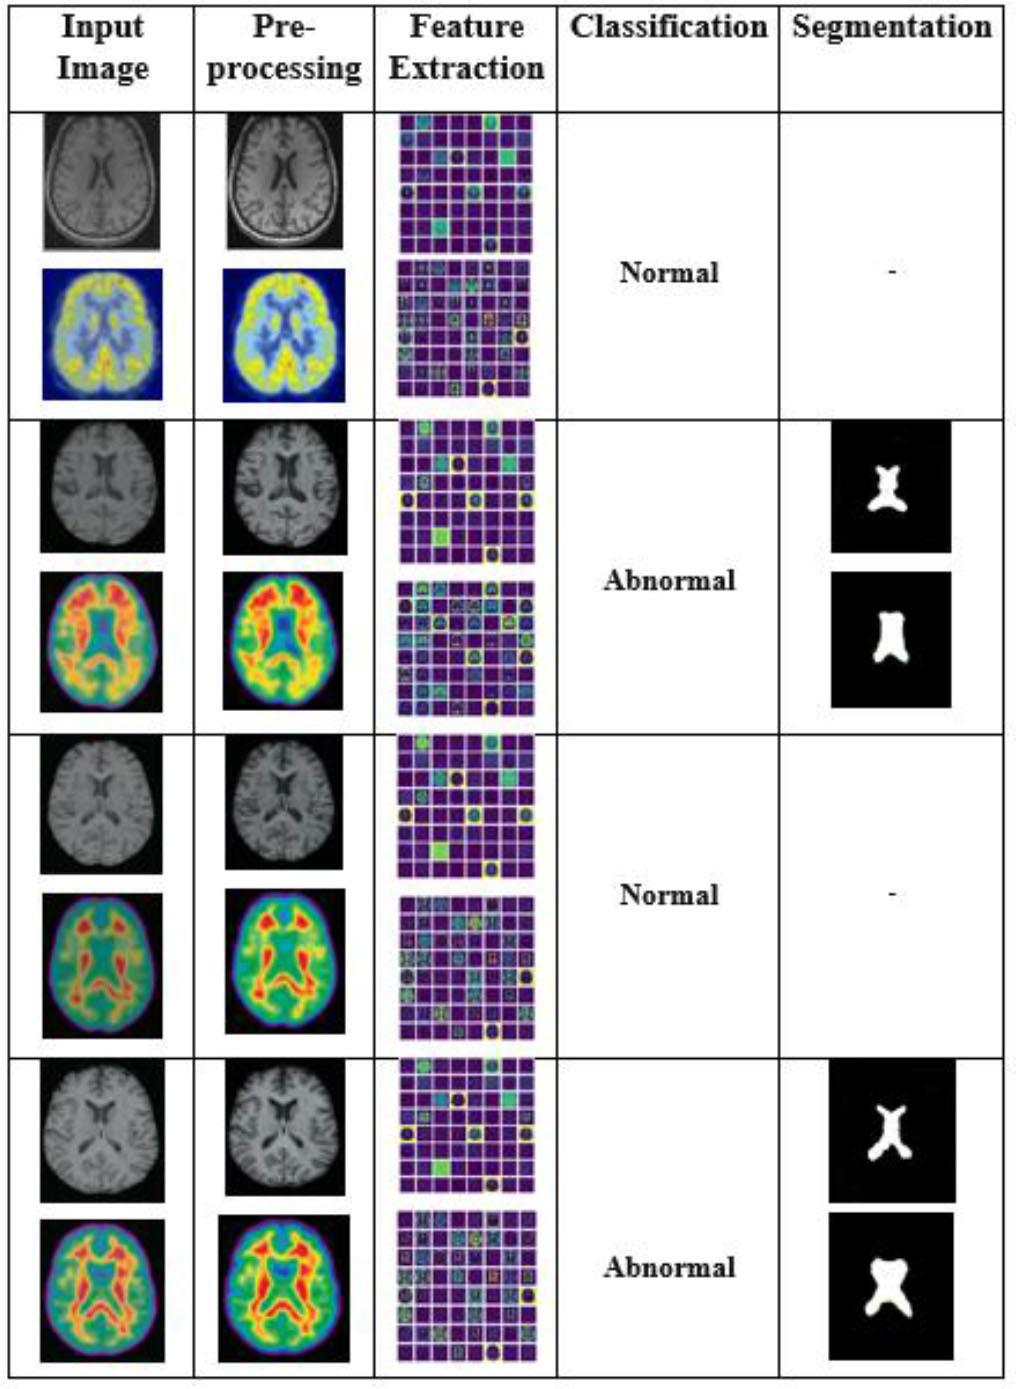

Fig. 4 illustrates the results of the proposed AD-HOLDER classification pipeline using features. Column 1 contains input dual images collected from the OASIS dataset. These dual modalities capture both structural and statistical features of the brain, which are crucial for early AD identification. Column 2 shows the enhanced images using a DIP filter to improve image quality. Features are extracted using HOG in column 3. Structural features are derived from the MRI images, representing anatomical aspects such as tissue loss. Statistical features are extracted from the PET images, capturing metabolic changes typical of Alzheimer’s progression. The dual features extracted from MRI and PET images are passed to an LGBM classifier, which categorizes them as normal or abnormal, as shown in column 4. The abnormal cases are fed into the next phase for tumor segmentation in column 5.

Experimental results of the proposed AD-HOLDER methodology.